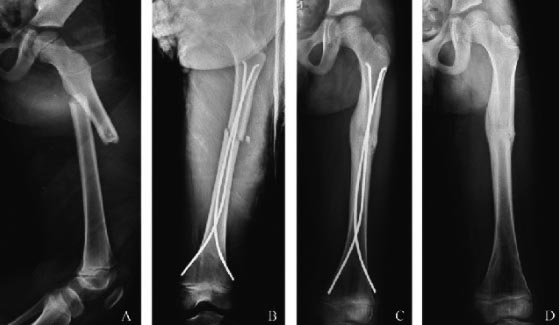

Эластичные титановые спицы. Закрыто.

Полностью согласен! Либо эластичные стержни Эндера, либо вытяжение.

Из-за того, что перелом проксимальный и оскольчатый, фиксация Нанси не будет достаточно стабильна. Можно наложить монолатеральный Ортофикс. Позволит быструю мобилизацию и даст сращение в желаемой позиции.

Мы бы тоже выбрали блокированный гвоздь. Мучение ходить с аппаратом - ещё то, не говоря уже о скелетном вытяжении и гипсе. ESIN не даст хорошей стабильности.